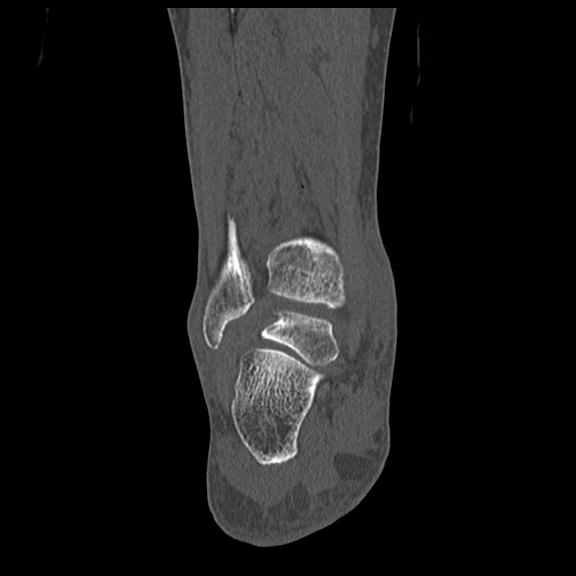

102755 1/4 2R 1/15 2R 右足関節 68歳女性 右三果脱臼骨折